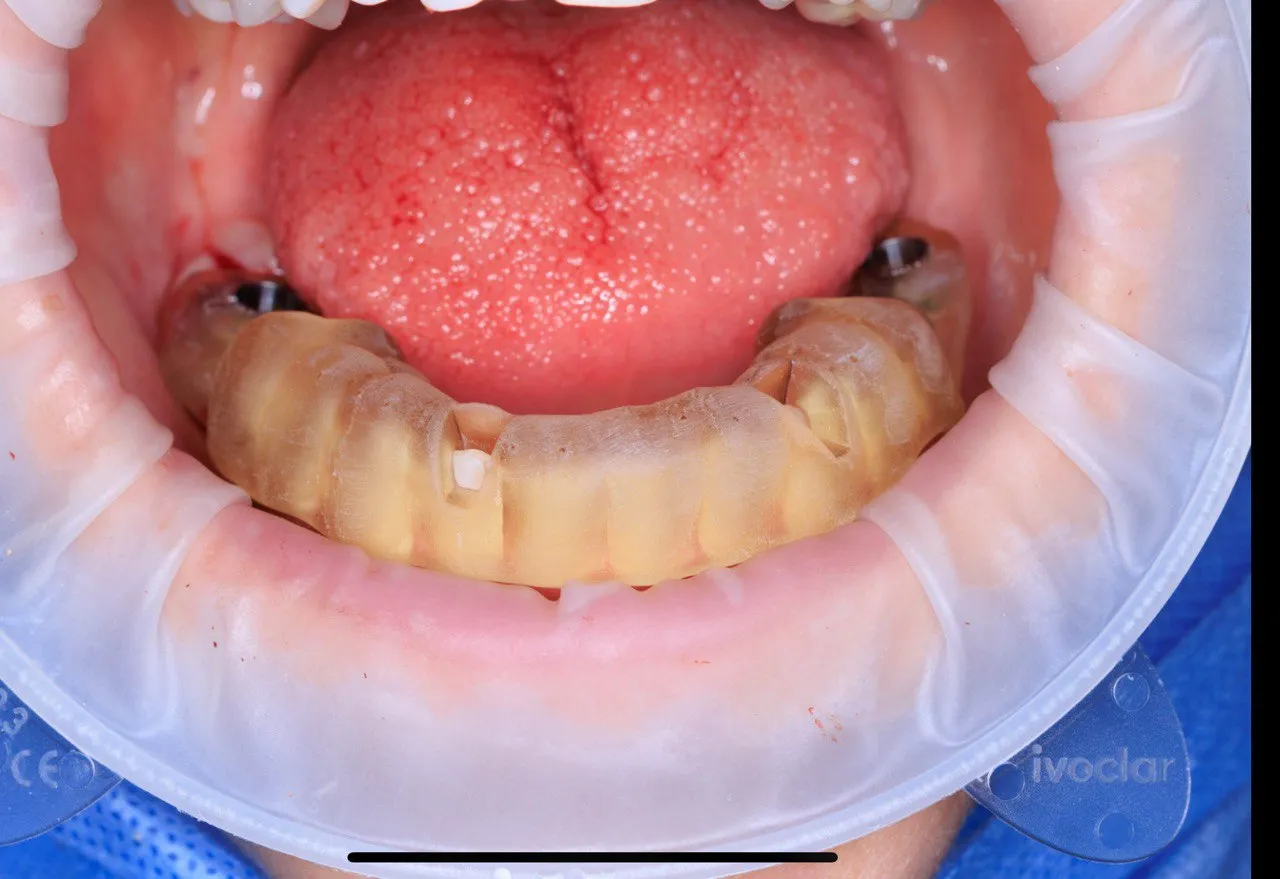

Dual Arch Rehabilitation — All-on-4 & All-on-6

Complete upper and lower jaw rehabilitation. All-on-4 concept for maxilla and All-on-6 for mandible with custom surgical guides.